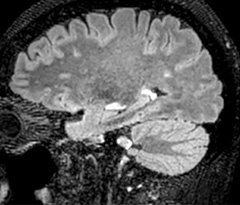

Improving scan time and/or spatial resolution

A two year follow-up scan of a CPA meningioma using both Ingenia 3.0T without CS and Ingenia Elition 3.0T with Compressed SENSE allows for a nice comparison to demonstrate the protocol improvements achieved on the Elition: 3D FLAIR has a shortened scan time, improved SNR and still the same spatial resolution. BrainView (3D T1 TSE) has improved spatial resolution and SNR with shortened scan time. For 3D T2 Drive the spatial resolution has been improved. 3D THRIVE used to have an interpolated 0.8 mm slice thickness, but true thickness at 1.6 mm, so that axial slices displayed a decent quality, but reformats were suboptimal.

Compressed SENSE is used on Elition to improve spatial resolution and reduce the non-interpolated slice thickness to allow smoothly reformatted images. Total scan time (adding SmartBrain and an additional b2000 diffusion) was 13:19 on Ingenia, and is now reduced to 10:42 on Ingenia Elition.

Ingenia 3.0T (without Compressed SENSE)

3D FLAIR (without Compressed SENSE)

3D FLAIR

1.0 x 1.0 x 1.0 mm*

4:24 min.

3D TSE T1w (without Compressed SENSE)

3D TSE T1w

1.0 x 1.0 x 1.2 mm*

2:40 min.

3D T2w Drive (without Compressed SENSE)

3D T2w Drive

0.8 x 0.8 x 1.0 mm*

3:05 min.

3D T1w THRIVE (without Compressed SENSE)

3D T1w THRIVE

0.8 x 0.8 x 1.6 mm*

1:30 min.

Ingenia Elition 3.0T with Compressed SENSE

3D FLAIR (with Compressed SENSE)

2:50 min.

3D TSE T1w (with Compressed SENSE)

2:10 min.

3D T2w Drive (with Compressed SENSE)

0.7 x 0.7 x 0.7 mm*

2:52 min.

3D T1w THRIVE (with Compressed SENSE)

0.7 x 0.7 x 0.8 mm*

*true voxel size, without interpolation